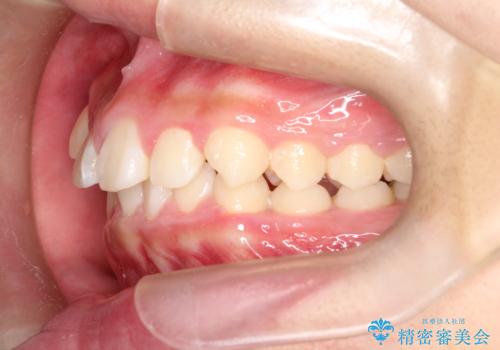

八重歯・歯並びのデコボコとディープバイトを改善した抜歯ワイヤー矯正症例

- 八重歯と咬み合わせを治したいを主訴にご来院された患者様です。

矯正の精密検査の結果上顎左右4番の計2本を抜歯し、審美性に配慮したワイヤー矯正装置(審美装置)を用いて治療を行いました。

八重歯などの歯列のデコボコが綺麗に改善され、患者様にも大変喜んでいただけました。また、咬み合わせが深い「ディープバイト」も併せて改善し、見た目だけでなく機能面でもバランスの取れた咬合を獲得しています。